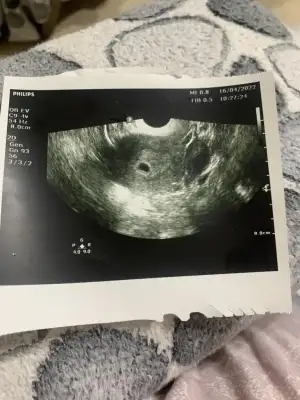

Merhaba.Canım bende de var hala çok az az iki gündür doktorumla konuştum sabah takip et bol bol dinlen dedi. Artip yoğun olması sıkıntı ama şu an için bir şey yok anladığım kadarıyla. Bende adet dönemi de aynı oldu sonra bebişi gördük o yüzden rahatım. İlişkiye girmeyin dedi bir de ama zaten girmiyoruz şu an bir sıkıntı olmasın diye

Normal adet olur gibi mi oldu kanamalariniz?